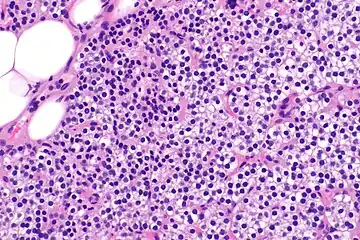

Parathyroid hyperplasia medium mag. -

Parathyroid hyperplasia high mag.

Primary hyperplasia of the parathyroid gland, results from both hypocalcaemia and increased phosphate levels by decreasing expression of calcium sensing receptors and vitamin D receptors at the parathyroid gland.[8][4] These decreases in receptor expression lead to hyperfunctioning of the parathyroid. Hyperfunction of the parathyroid gland is thought to exacerbate primary hyperplasia which evolves further to a secondary more aggressive hyperplasia. Histologically, these hyperplasic glands can be either diffuse or nodular.[24] Primary hyperplasia, usually resulting in diffuse polyclonal growth is manly related to reversible secondary hyperparathyroidism. Secondary hyperplasia of the parathyroid gland is more often a nodular, monoclonal growth that sustains secondary hyperparathyroidism and is the catalyst in the progression to tertiary hyperparathyroidism. Nodular hyperplastic glands in tertiary hyperparathyroidism are distinctly larger in both absolute size and weight up to 20-40-fold increases have been reported.[25][26][24]

Parathyroid glands are normally composed of chief cells, adipocytes and scattered oxyphil cells.[27][14] Chief cells are thought to be responsible for the production, storage and secretion of parathyroid hormone. These cells appear light and dark with a prominent Golgi body and endoplasmic reticulum. In electron micrographs, secretory vesicles can be seen in and around the Golgi and at the cell membrane. These cells also contain prominent cytoplasmic adipose.[27][14] Upon onset of hyperplasia these cells are described as having a nodular pattern with enlargement of protein synthesis machinery such as the endoplasmic reticulum and Golgi. Increased secretory vesicles are seen and decreased intercellular fat is characteristic.[27][24] Oxyphil cells also appear hyperplasic however, these cells are much less prominent.

Biochemically, there are changes in function between normal and nodular hyperplastic parathyroid glands. These changes involve proto-oncogene expression and activation of proliferative pathways while inactivating apoptotic pathways.[28] In nodular parathyroid tissue increased expression of TGF-a, a growth factor, and EGFR, its receptor, results in aggressive proliferation and further downregulation of vitamin D receptors, which act to suppress hormone secretions.[25][8][28] Furthermore, the proliferative marker, Ki67 is seen to be highly expressed in the secondary nodular hyperplastic state.[28][25] Tumour suppressor genes have also been highlighted as being silenced or degraded in nodular hyperplastic parathyroid tissue.[8][28] One such gene, p53, has been shown to regulate multiple tumour suppressor pathways and in tumorigenesis can be degraded by b-catenin. This pathway, in some aspect, is mediated by CACYBP, which is highly expressed in nodular parathyroid hyperplasia.[28]